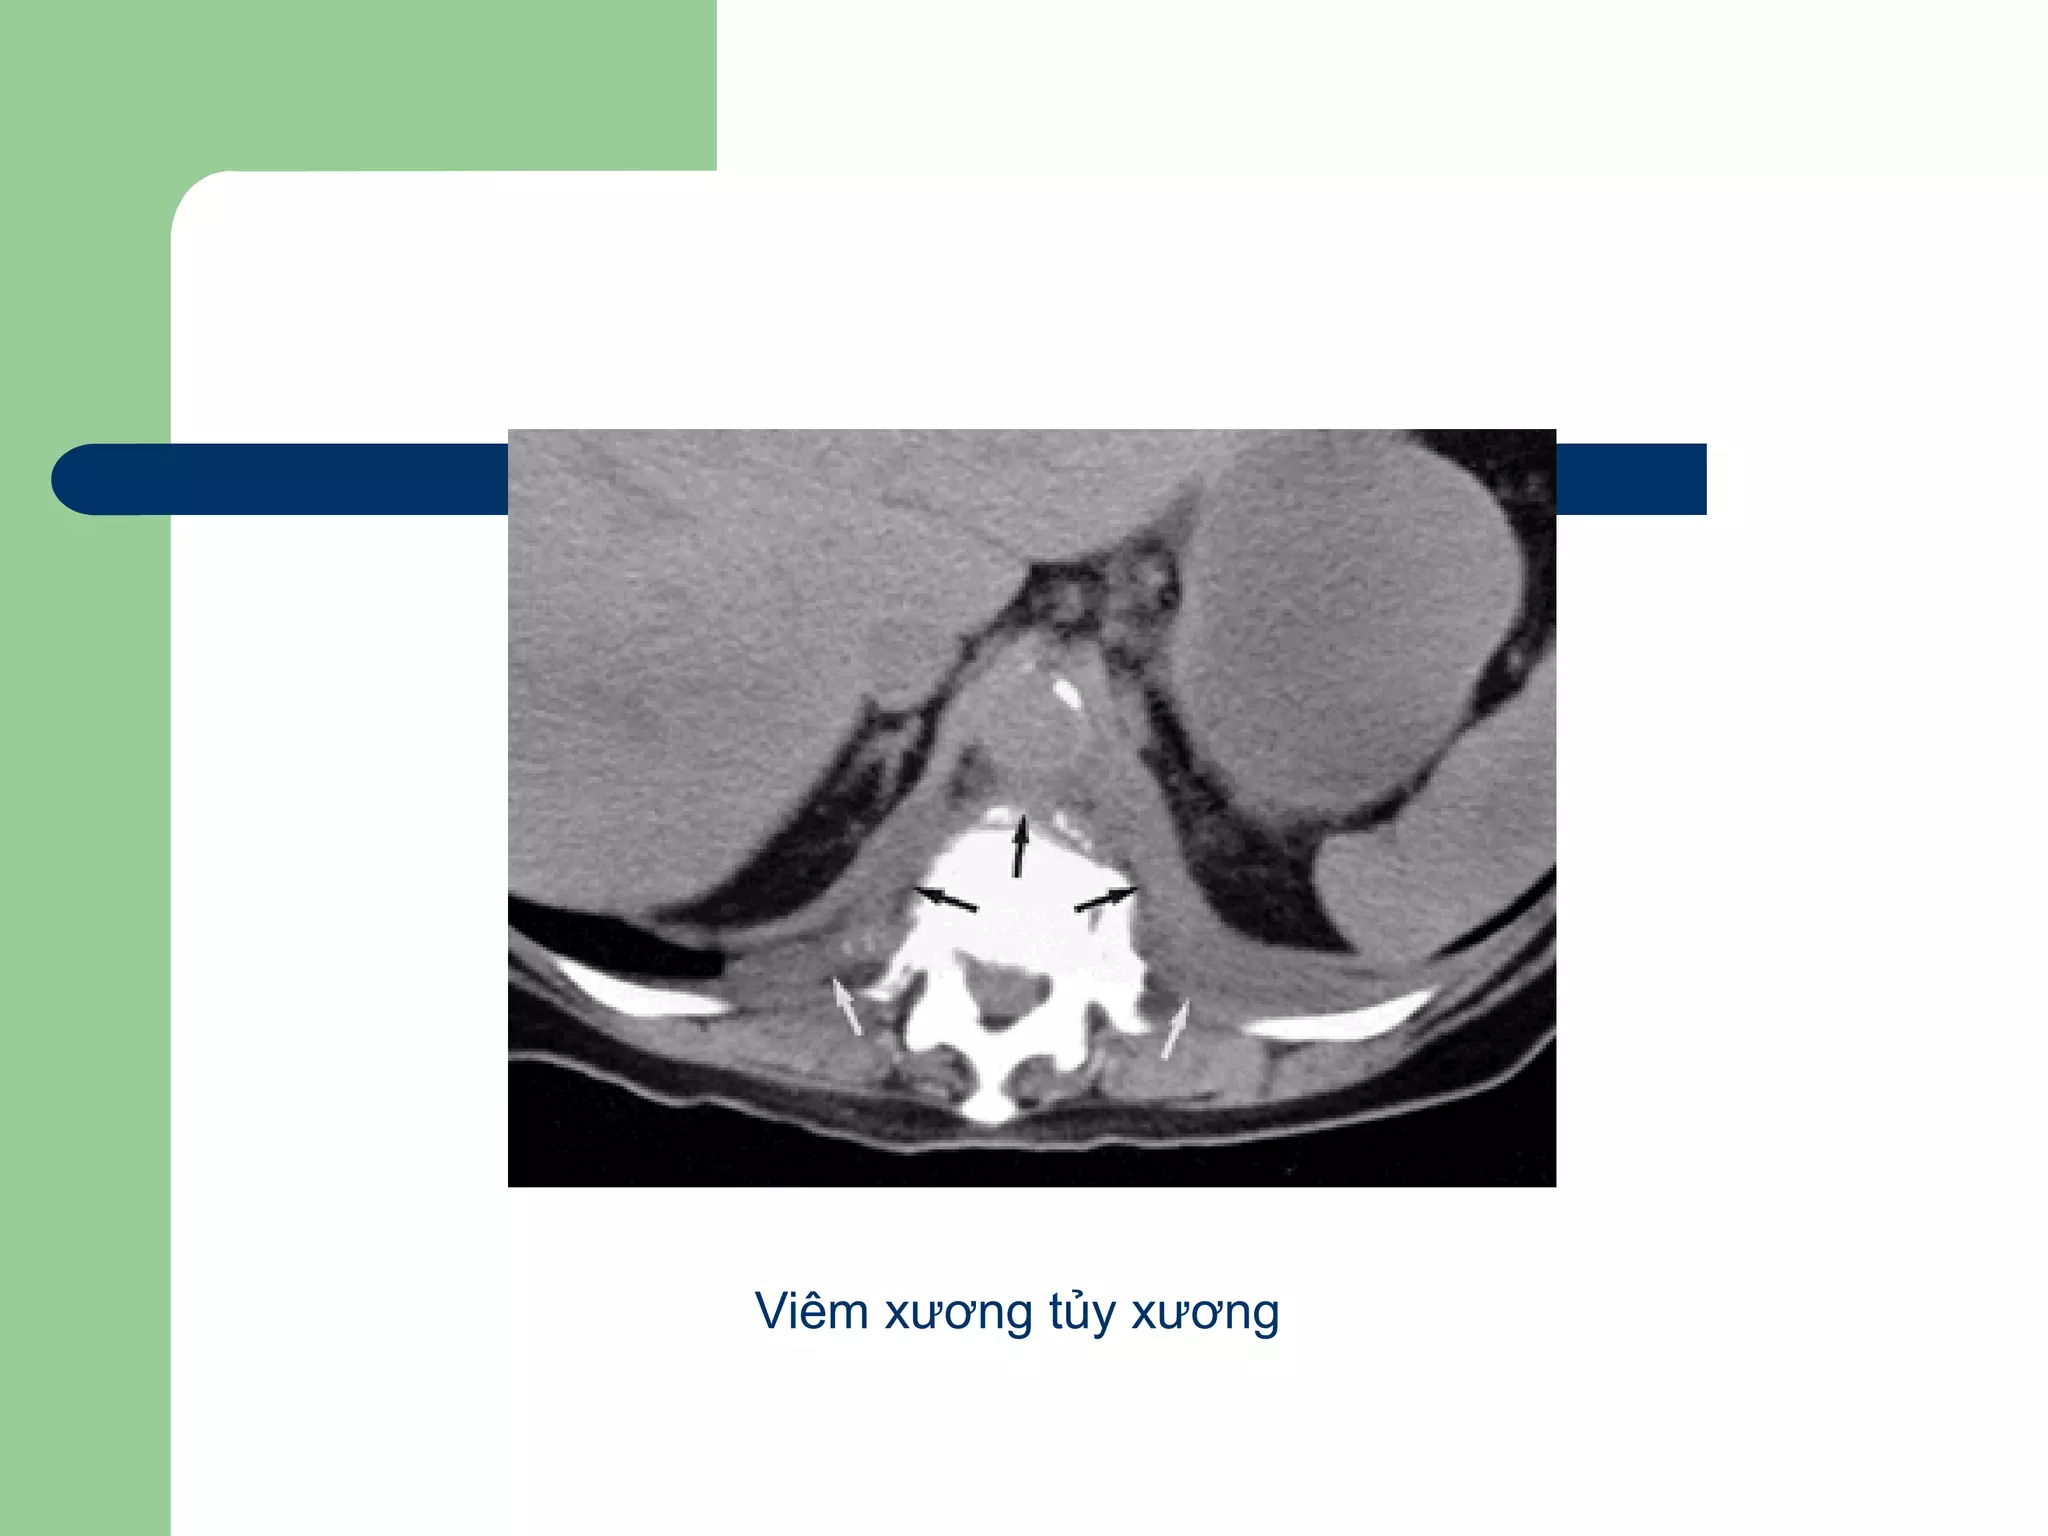

Bệnh lý thành ngực

Viêm nhiễm

 Viêm xương tủy xương, viêm phần mềm

hay từ phổi- màng phổi (lao, nấm…)

 Hình ảnh CT:

– Thay đổi cấu trúc, hình dáng

– Có thể xóa lớp mỡ ngoài màng phổi

– Tăng quang mạnh ở thành tổn thương

Viêm xương tủy xương